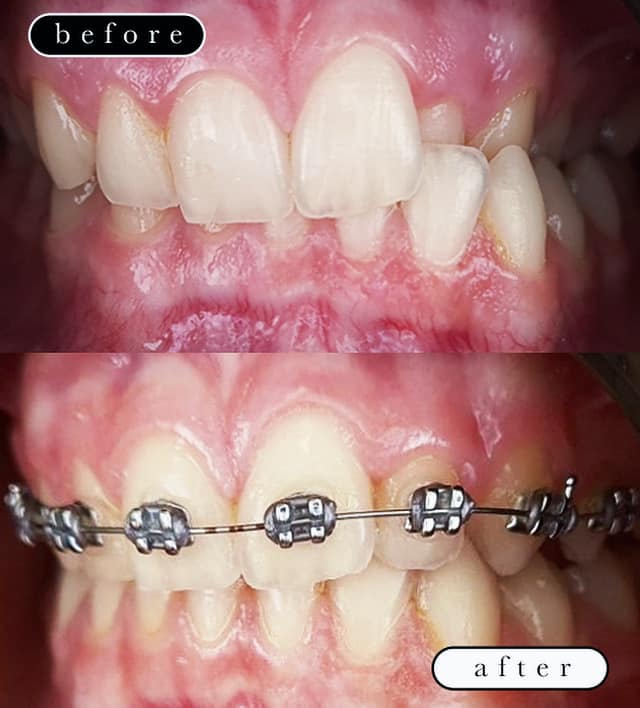

O našoj kvaliteti najbolje govore naši rezultati!

Centar za ortodonciju Petra Džapo